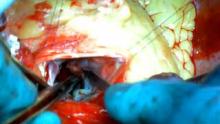

Cardiopulmonary bypass was initiated via an aortic and right atrial cannulation. Through a transaortic approach, an extended left ventricular septal myectomy was performed starting below the nadir of the right coronary cusp and was directed in an anticlockwise direction towards the commissure between the left and non-coronary cusps. Further resection was performed down in the midventricle to ensure complete elimination of the gradient. The anterolateral papillary muscle of the mitral valve was mobilized as it was fused to the interventricular septum.